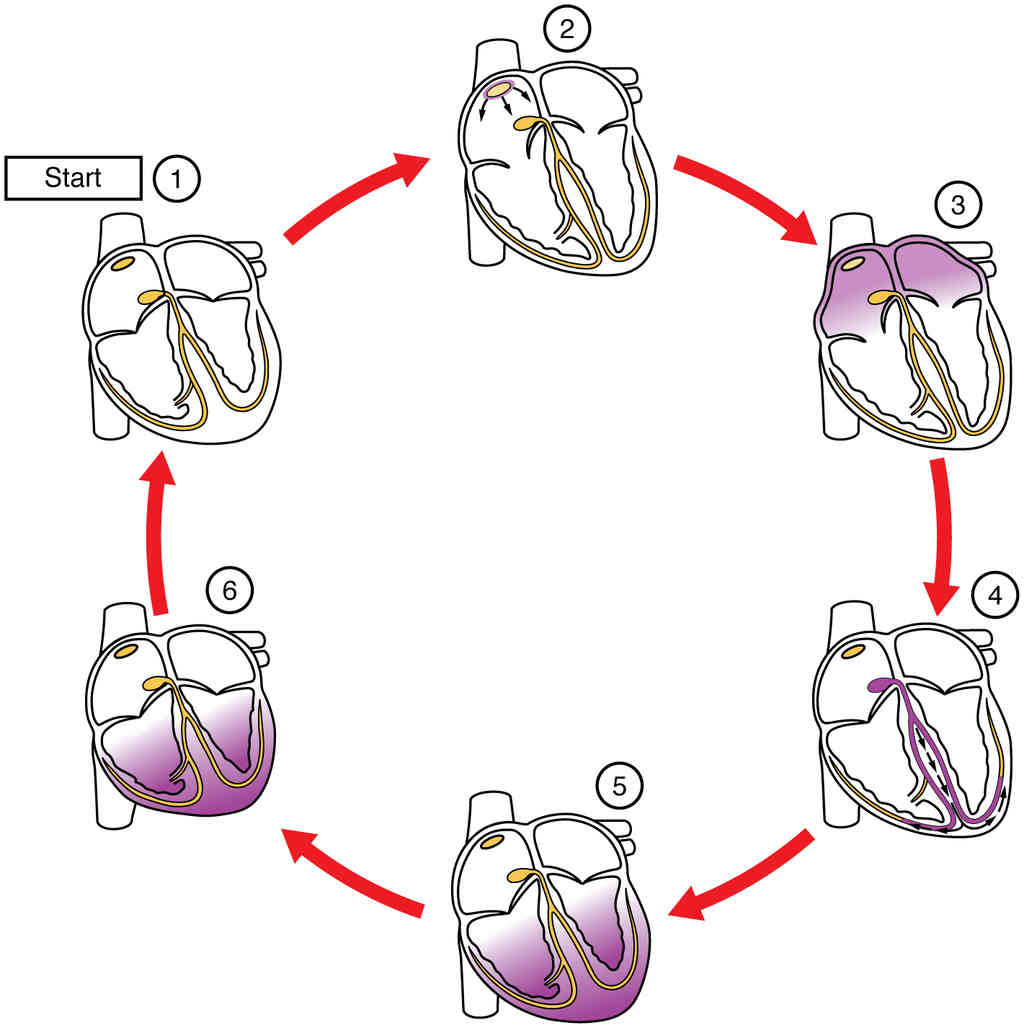

This page is under construction. For now, it is just a resource of the images found in the OpenStax Anatomy and Physiology Handbook. It wil slowly change into a revision tool. Each slide has a number. Use this to refer to the slide. When completed, it will have an unlabelled section, with labelled slides in parallel. On the unlabelled slides, write your answer and use the labelled slide to assess yourself. Keep track by also noting the number on each slide. Improvement at each attempt is important, more so than full marks on a first attempt.